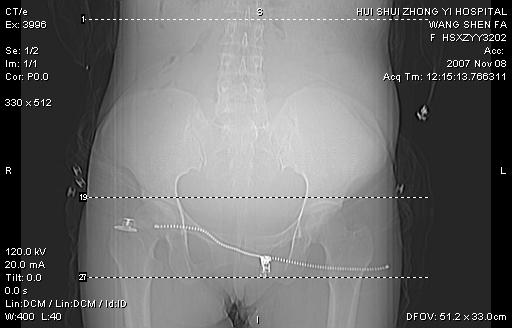

标题: CT10389:女,38岁,腹部巨大包块 [打印本页]

标题: CT10389:女,38岁,腹部巨大包块

腹部巨大包块半年,质硬,边界不清。